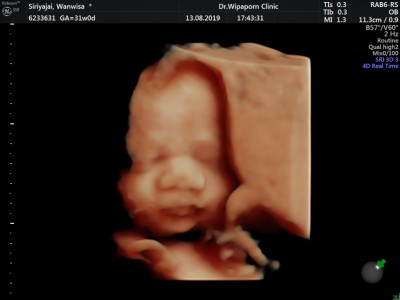

บ้านนี้ซาวตอน 28 วีคค่ะแม่